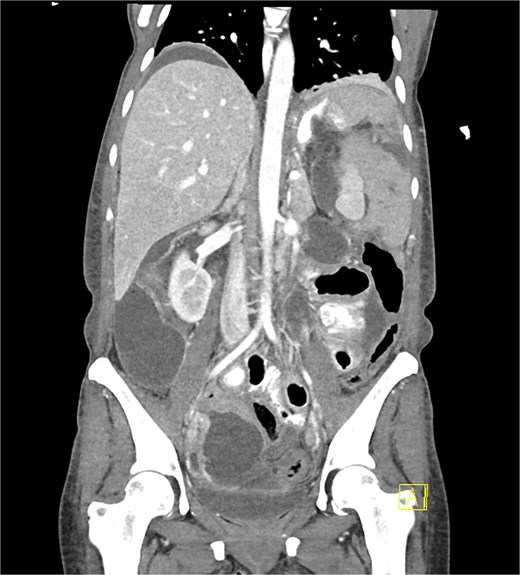

Unfortunately, day six post-operatively she represented with significant abdominal pain with a WCC of 12.5 and a CRP of 527. A CT demonstrated a large leak from the proximal stomach with widespread fluid and pneumoperitoneum throughout the abdomen (Fig. 3). She proceeded to an urgent diagnostic laparoscopy which found four quadrant peritonitis with food matter and purulent collections throughout the abdomen. A washout was performed laparoscopically though the defect was not able to be identified, and large bore drains were placed at the presumed leak site at the proximal stomach with the aim to transfer to a quaternary center for ongoing care under a specialized unit experienced in management of complex bariatric complications.

Coronal portal venous phase CT scan with oral contrast of the abdomen and pelvis demonstrating the proximal gastric leak with large volume contrast extravasation into the left upper quadrant and widespread intra-abdominal fluid with pneumoperitoneum.